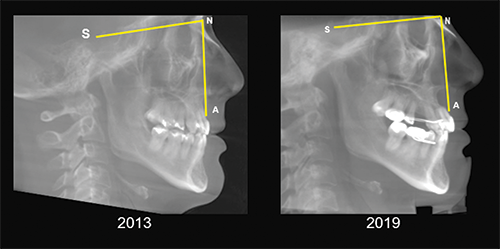

Fig. 4: CBCT-generated lateral cephalograms pre-AGGA and at end-stage AGGA treatment. Patient-provided scans.

This growth was erroneously measured using the cephalometric SNA measurement. Upon closer examination, the maxilla did not grow forward (A-point) as claimed by AGGA providers. The claim of maxillary forward growth was incorrectly measured by using the facial root surface of an upper central incisor as A-point (Fig. 5). Misidentifying the A-point in this way contributed to the belief that maxillary forward growth had occurred.

Ignoring Biological Limitations

Fig. 5: Improper A-point identification on CBCT-generated lateral cephalograms taken at pre-AGGA treatment (2013) and at end-stage AGGA treatment (2019) falsely implies forward growth of the maxilla. Patient-provided scans.

In reality, most of the movement in this case and in the majority of AGGA patients occurred through distalization of molars in the posterior region, with some forward movement of the upper anterior segment. The fatuous “claimed growth” was supported by an inappropriate A-point location, a common error with cephalometric measurements.